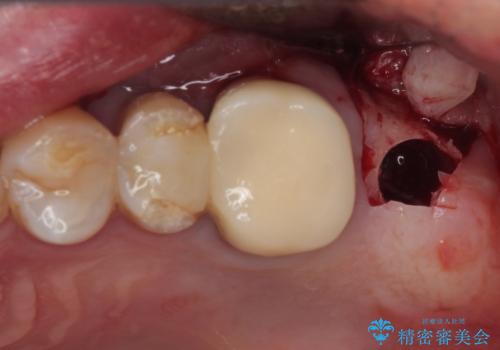

前歯は根管治療が必要となり、元々舌側に入り込んでいた左上2番目の歯は歯周外科処置により歯肉ラインを整えることとしました。

欠損部位は傾斜歯軸を起き上がらせることができたため、オールセラミッククブリッジにて補綴治療を行いました。